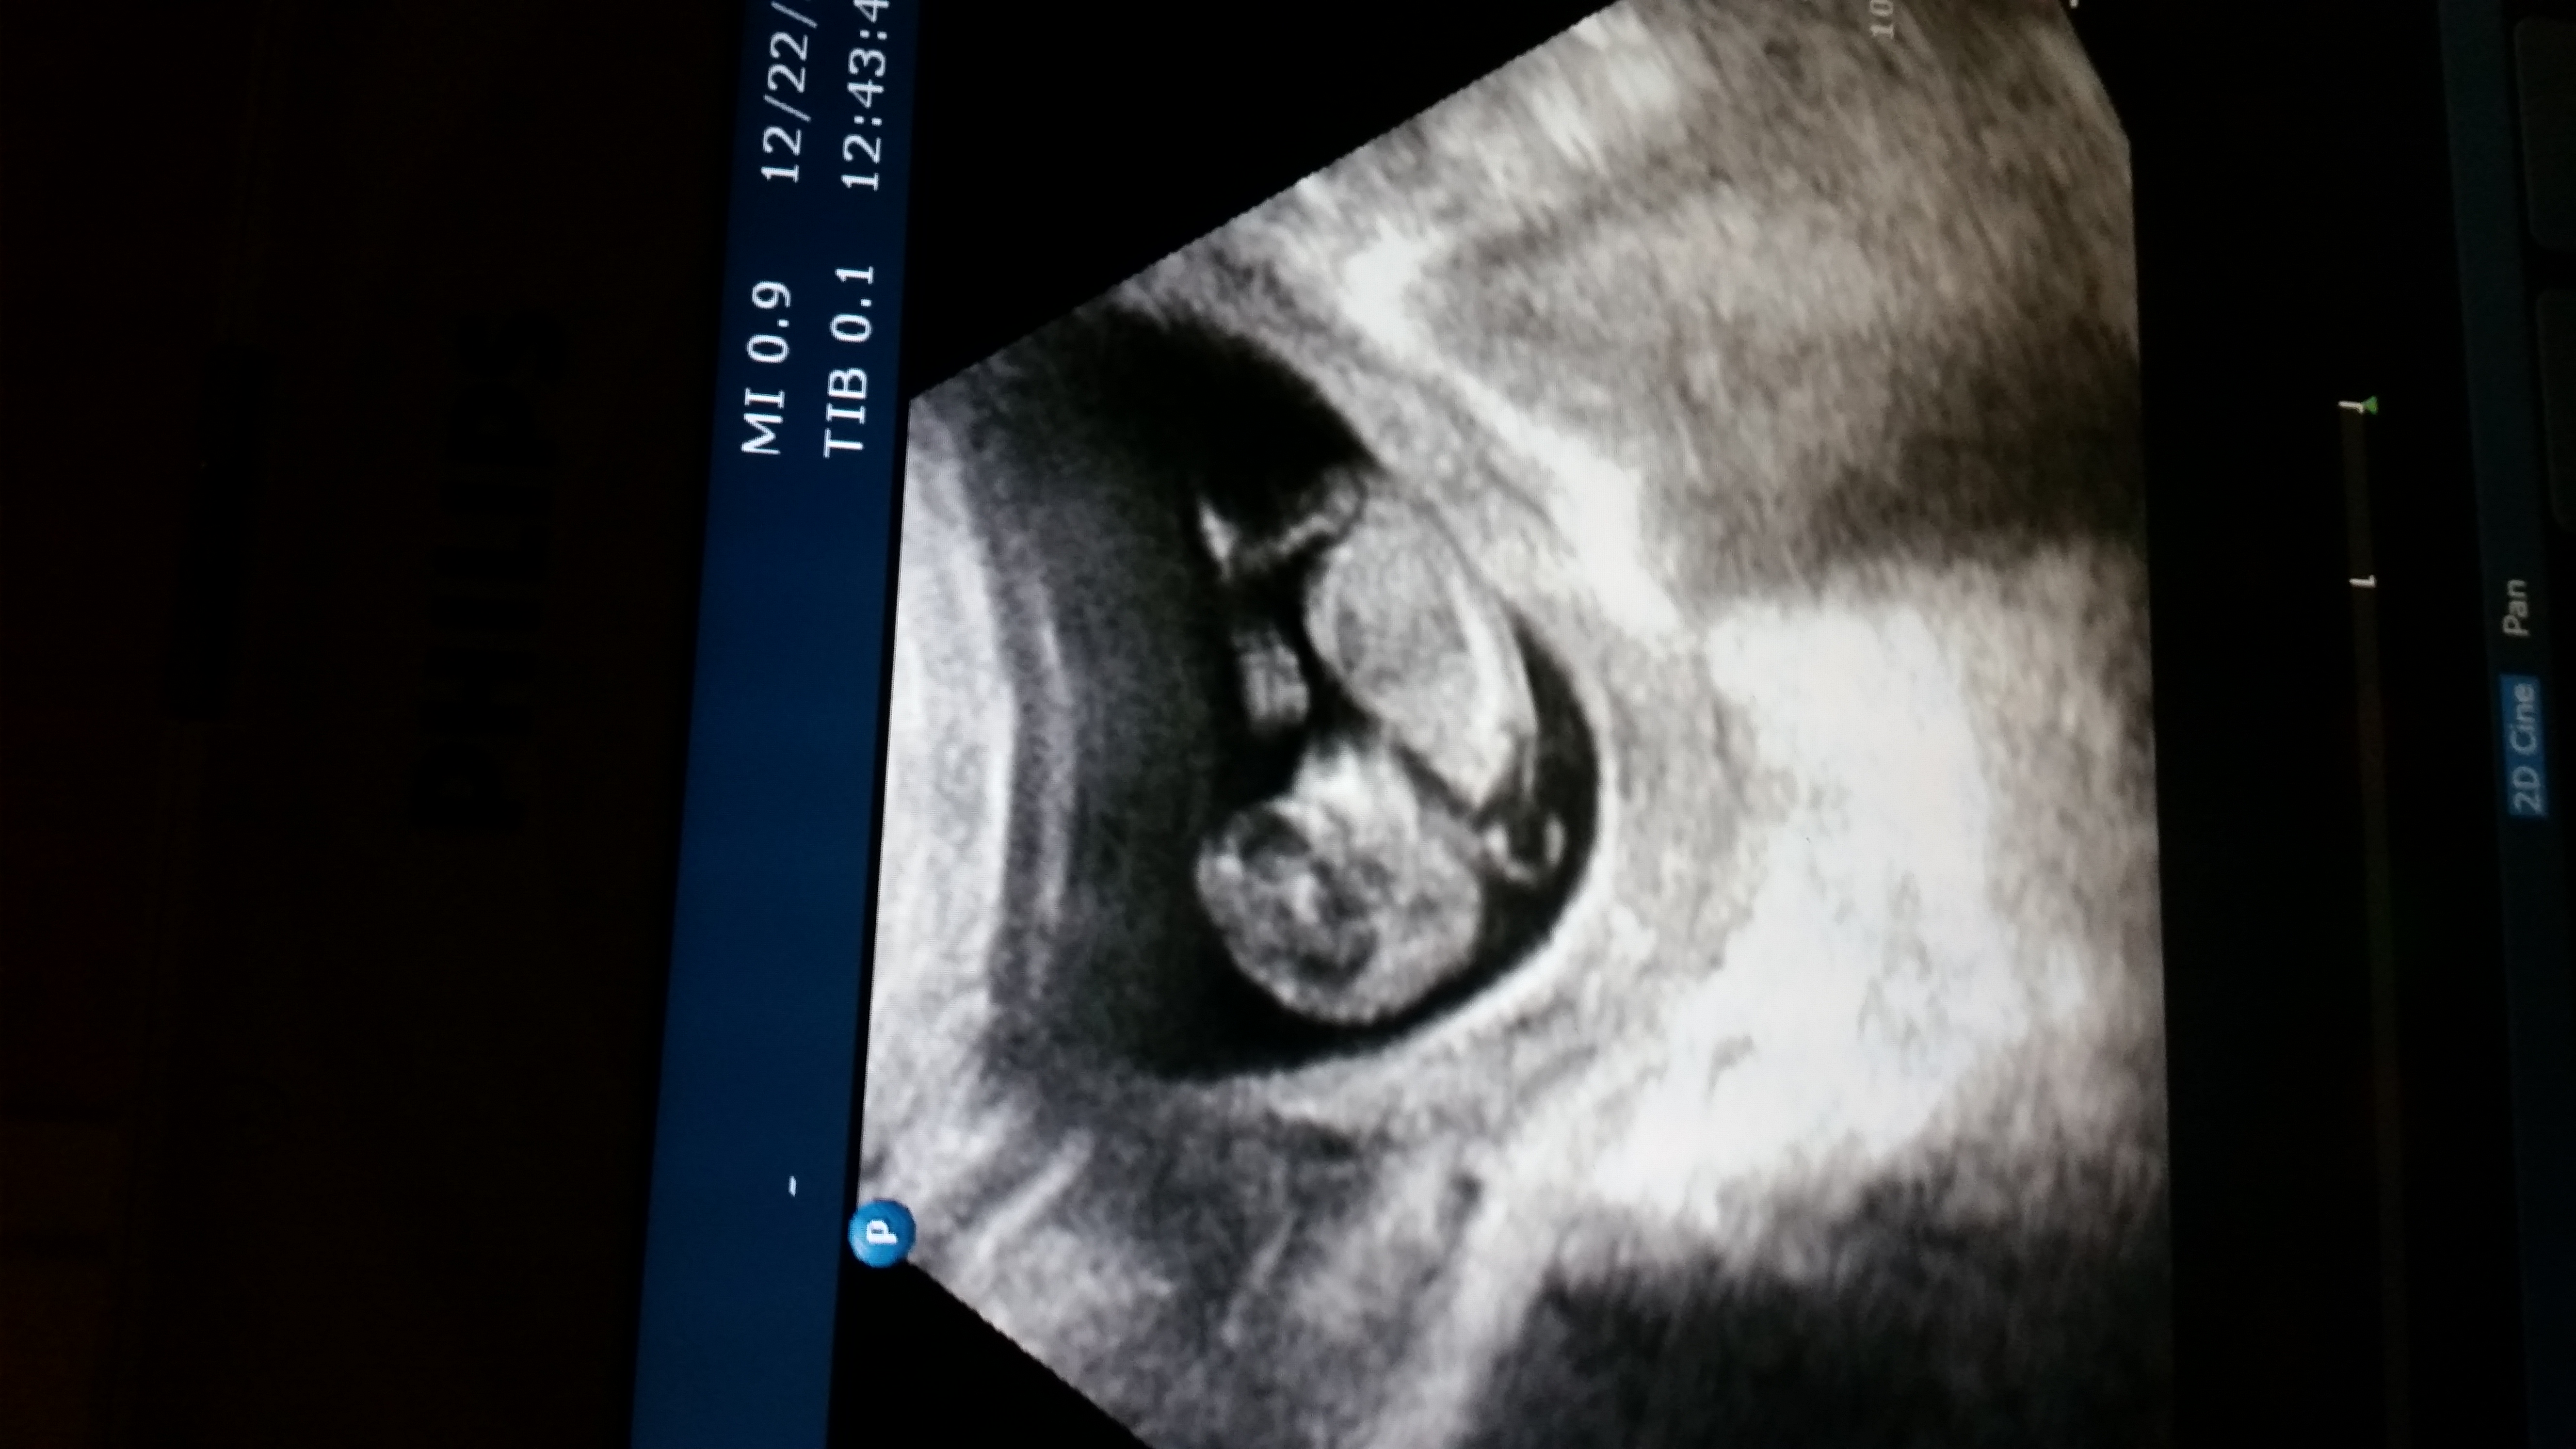

Hi there, I am so anxious to find out the sex of my baby. What do you guys think? Look at head shape and area between legs :)Attachment 22840Attachment 22841Attachment 22841

You guys are much more qualified than I am for sure lol. But am I looking TOO into between its legs? I feel as if I can see something there. It could very well be my imagination, or a bone or something of that sort.

So am I looking too into that nub shaped thing right by the leg? Call me crazy, but I see something there. Even a friend of mine had said the same thing. Or is that a bone? Lol

I see what you "think" you see and yes that is bone. Sadly no nub but a boyish skull!

Nahri thank you so much! Yes I pulled my girls ultrasound pics out and the skulls look so much different. This one was more boxed shape. And haha thank you for clarifying it is a bone LOL